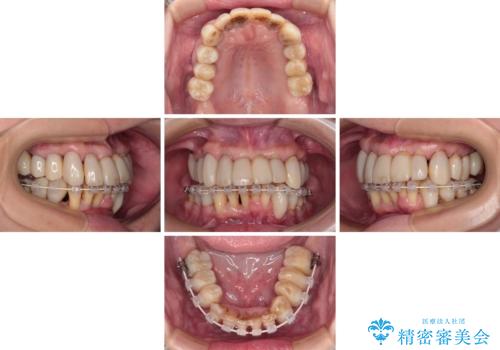

- 矯正装置

- 審美装置

2~3年は早く終了する予定でしたが、途中で体調を崩されて来院されない時期が続いたため、非常に長期間の治療となりました。

上顎口蓋からの堅い歯肉を移植する角化歯肉移植術を行いたかったのですが、体調不良から実施しなかったため、最終補綴物であるオールセラミッククラウンを装着した後に、知覚過敏や境目が見てしまうといった問題が一部で発生いたしました。

最終的には痛みや違和感のない状態にて治療を終えることができました。